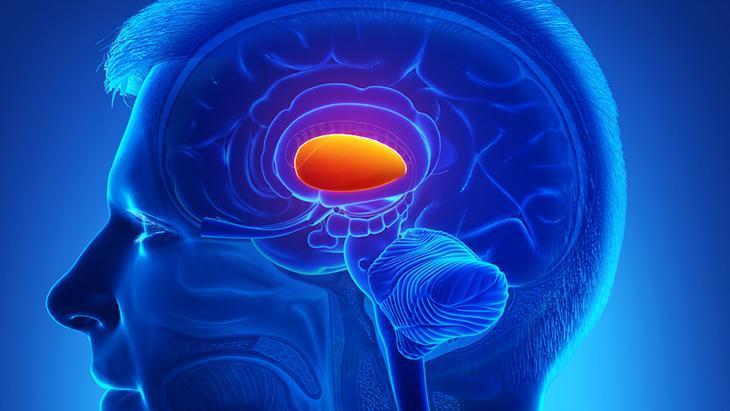

Omurilik, vücuttaki iletişim yolu olan sinir liflerinin bir kısmını içerir. Bu sinir lifleri, beyin ile vücut arasında iletişimi sağlar, vücuttaki hareket ve duyu işlevlerini kontrol eder. Omurilik felci, omurilikteki hasar sonucu vücudun belirli bölgelerinde veya tüm vücutta hissizlik, kuvvetsizlik veya felç gibi motor ve duyusal işlev kayıplarına yol açan bir durumdur.

Epidural Stimülasyon, omurilik felçli hastalara umut veren bir çözüm sunuyor. Bu yenilikçi teknoloji, omuriliğe yerleştirilen özel bir pil aracılığıyla sinir uyarımını gerçekleştirerek kaybedilen hareket yeteneğini geri kazandırmayı amaçlıyor.